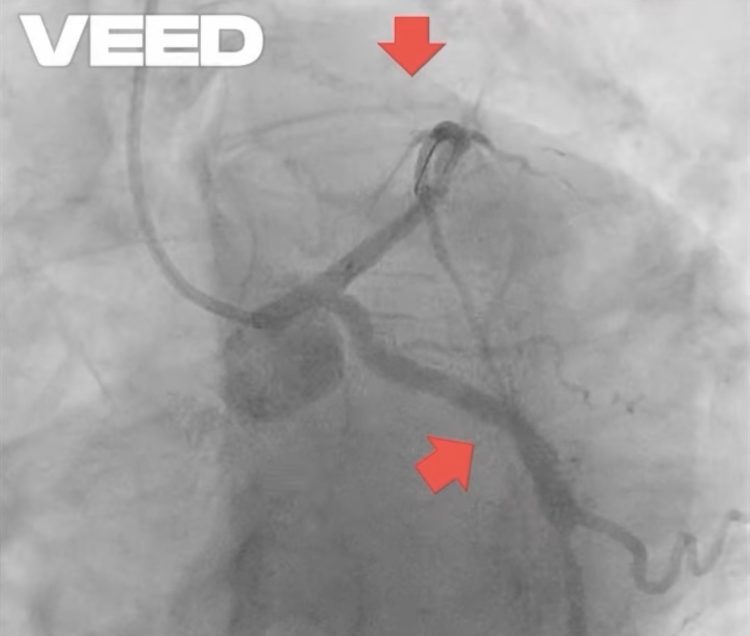

Ceea ce s-a întâmplat se numește stenoză intrastent – o îngustare a arterei exact în interiorul stentului. Aceasta poate apărea fie prin proliferare tisulară, fie prin tromboză de stent, un eveniment extrem de periculos, frecvent favorizat de întreruperea tratamentului antiagregant.